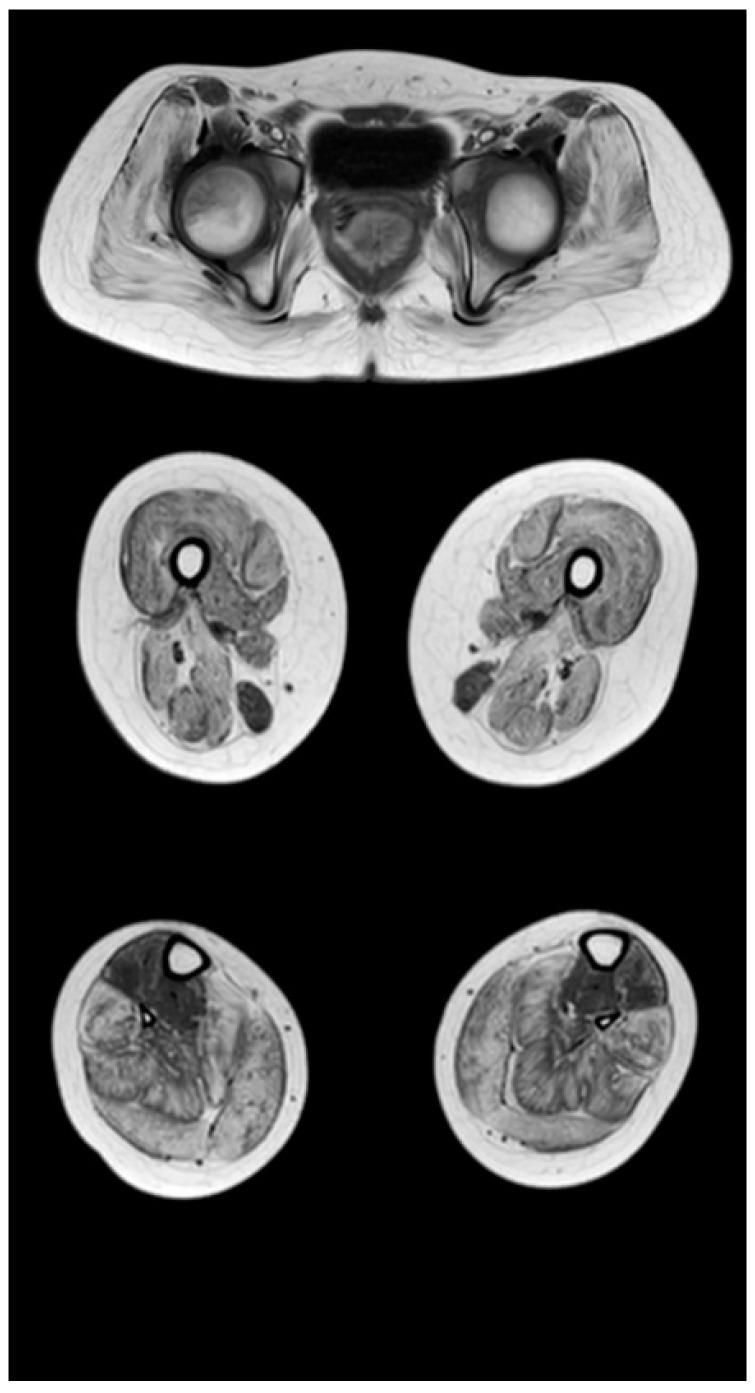

The research was aimed on the study of motor capabilities on the Motor Function Measure (MFM) scale in ambulant and non-ambulant patients with Duchenne muscular dystrophy, and to conduct a correlation analysis between the results of the MFM scale and Magnetic Resonance Imaging (MRI) data. A total of 46 boys who had genetically confirmed Duchenne muscular dystrophy (age from 2.1 to 16.7 years) and were in clinical rehabilitation were investigated. An assessment was performed according to the Motor Function Measure scale (subsections D1, D2, D3, and the total score), an MRI obtaining T1-VI of the muscles of the pelvic girdle was conducted, and the thighs and lower legs were further assessed in terms of the severity of fibrous-fat degeneration according to the Mercuri scale. In ambulant patients, the ability to stand up and move (D1) was 74.4%, axial and proximal motor functions (D2)—97.6%, distal motor functions (D3)—96.2%, and total score was 87.9%. In non-ambulant patients, the ability to stand up and move (D1) was 1.7%, axial and proximal motor functions (D2)—47%, distal motor functions (D3)—67.5%, and the total score—33.1%. A high inverse correlation (r = −0.7, p < 0.05) of the MRI data of the pelvic girdle and thighs with tasks D1, as well as a noticeable inverse correlation with tasks D2 (r = −0.6, p < 0.05) of the scale MFM, were revealed in the ambulant group of patients. In the non-ambulant group of patients, the MRI data of the lower legs muscles were characterized by a high inverse correlation (r = −0.7, p < 0.05) with tasks D3 and a noticeable inverse correlation (r = −0.6, p < 0.05) with tasks D1 of the MFM scale. Conclusion: The Motor Function Measure scale allows effective assessment of the motor capabilities of patients with Duchenne muscular dystrophy at different stages of the disease, which is confirmed by visualization of fibro-fatty muscle replacement.

本研究旨在研究肌营养不良症(Duchenne muscular dystrophy,DMD)患者的运动功能,使用运动功能测量(Motor Function Measure,MFM)量表评估其在活动和非活动患者中的表现,并对 MFM 量表的结果与磁共振成像(Magnetic Resonance Imaging,MRI)数据进行相关性分析。本研究共纳入了 46 名经基因确诊的 DMD 男孩(年龄为 2.1-16.7 岁),他们均处于临床康复阶段。研究人员对这些患者进行了 MFM 量表(D1、D2、D3 亚组和总分)评估,并进行了骨盆带肌肉的 T1-VI MRI 检查,根据 Mercuri 量表对大腿和小腿的纤维脂肪变性严重程度进行了进一步评估。在活动患者中,站立和移动能力(D1)为 74.4%,轴向和近端运动功能(D2)为 97.6%,远端运动功能(D3)为 96.2%,总分为 87.9%。在非活动患者中,站立和移动能力(D1)为 1.7%,轴向和近端运动功能(D2)为 47%,远端运动功能(D3)为 67.5%,总分为 33.1%。在活动患者中,骨盆带和大腿 MRI 数据与任务 D1 之间存在高度负相关(r = -0.7,p < 0.05),与 MFM 量表的任务 D2 之间也存在显著的负相关(r = -0.6,p < 0.05)。在非活动患者中,小腿肌肉的 MRI 数据与任务 D3 之间存在高度负相关(r = -0.7,p < 0.05),与 MFM 量表的任务 D1 之间也存在显著的负相关(r = -0.6,p < 0.05)。结论:MFM 量表能够有效评估不同疾病阶段的 DMD 患者的运动能力,这一结论通过纤维脂肪肌肉替代的可视化得到了证实。